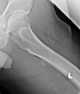

Calcific tendonitis

Calcific tendinitis is a form of tendinitis, a disorder characterized by deposits of hydroxyapatite (a crystalline calcium phosphate) in any tendon of the body, but most commonly in the tendons of the rotator cuff (shoulder), causing pain and inflammation. The condition is related to and may cause adhesive capsulitis ("frozen shoulder"). [Source: Wikipedia ]